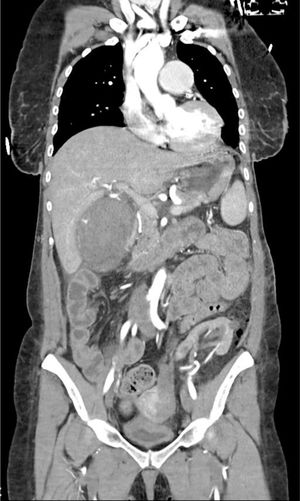

Paciente mujer de 47 años con antecedentes de nefropatía por inmunoglobulina A (IgA) que requirió trasplante renal en dos ocasiones y hemicolectomía derecha por perforación intestinal, en el posoperatorio inmediato de nefrectomía izquierda por neoplasia renal, presenta shock hipovolémico secundario a colecistitis necro-hemorrágica evidenciando sangrado activo en la tomografía axial computarizada (TAC) (figs. 1 y 2) realizada por sospecha de hemorragia posquirúrgica. Se efectúa una colecistectomía emergente encontrando 500 cc de contenido hemático en el interior de la vesícula y sangrado activo en el peritoneo parietal de la misma que cede tras la ligadura de la arteria cística. La paciente es dada de alta sin sufrir complicaciones.